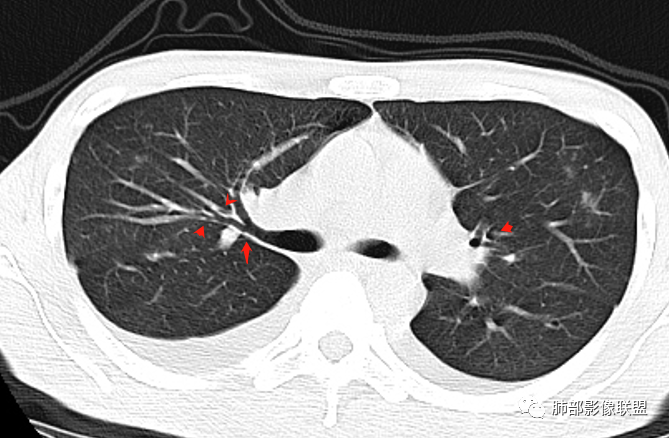

丽:青年男性,双下肢水肿,病史无肺部症状,化验白细胞明显减低;白蛋白低,提示双侧胸腔积液可能低蛋白所致。补体值降低提示自身免疫性疾病,影像见双肺散在结节样,斑片状高密度影及实变密度影,大部分沿支气管血管束分布,以右肺下叶为主,内可见充气支气管征,周围可见磨玻璃密度,并见多发小叶间隔增厚,伴心包少许积液,双肺病变,临床无症状,感染首先除外,结合腮腺病变,双下肢病变及化验检查,综合考虑自身免疫性疾病肺部改变

红星:病史资料:患者男,30岁,因“双小腿及双踝双足浮肿1周”入院。患者1周前无明显诱因下感双小腿及双踝双足浮肿,胸部CT示:两肺多发感染。尿酸增高,肝功能损害,两肺多发的结节状及片状的模糊阴影,小叶中心分布为主,病灶中心密度比较高,周围密度较淡,晕征,整体病灶比较单一,以渗出为主,两下肺分布,尤其是右下肺分布为甚,两侧胸腔积液,心包积液。心脏左心室明显增大。考虑肺部感染或者是血管炎的一些病变。个人认为,左心功能不全合并有肺水肿或者是血管炎的一些病变。

张延军:双肺多发斑片及结节状高密度影,边缘不清,结节周围伴晕征,前者沿支气管束分布呈实变影,内走形支气管通畅,临近肺组织见大片状磨玻璃影,界不清,中轴间质增厚,影像提示,支气管血管束周围及肺内间质为主病变,临床风免提示,考虑结蹄组织疾病肺内改变

中轴间质增厚轻微

双下肺淡薄GGO

小叶间隔增厚

沿支气管血管束分布斑片状更高密度影,部分实变

双侧胸腔积液,双下肺斑片状磨玻璃密度影,背景是大片状磨玻璃密度影,密度稍低一些。这个磨玻璃影非常弥漫,没有受局限,胸膜下不是很清楚,内部结构显示清楚,稍实变的区域也是,小叶间隔增厚,中轴间质也增厚。有些病变边缘有收缩,有轻度OP样特点,但是这些病变似乎密度非常均匀。